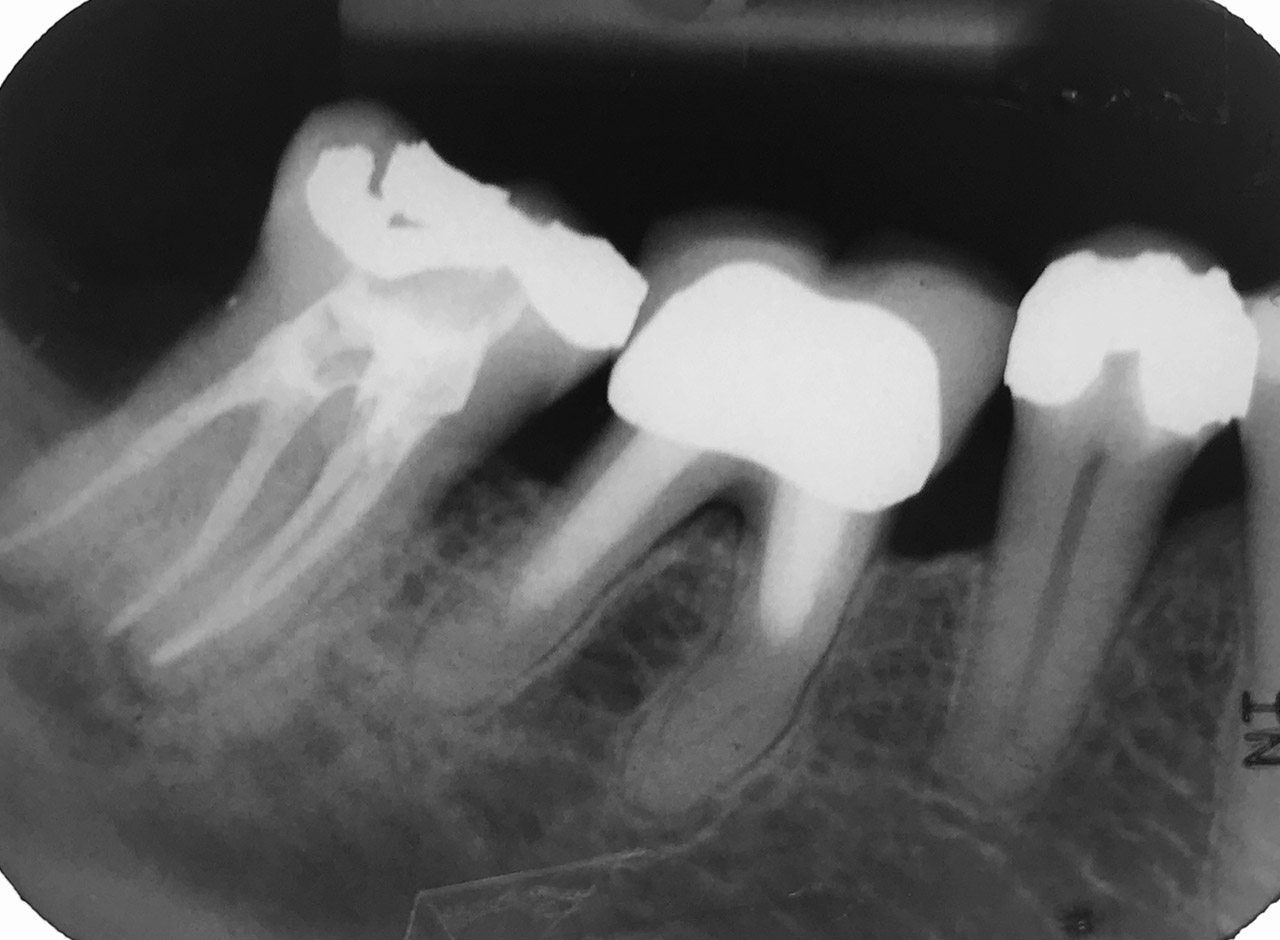

Wurzelbehandlung/Endodontie:

Massiver Paro-/Endodefekt bei den Zähnen 38&37. Extraktion von 38 (Weisheitszahn) und Wurzelbehandlung von 37 (4 Kanäle). Defekt vollständig ausgeheilt.